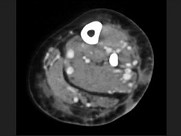

- 单项选择题男,16岁, 大腿可触及柔软、无痛性肿块,结合图像, 最可能的诊断是 ( )

A、滑膜肉瘤

B、脂肪肉瘤

C、脂肪瘤

D、血管瘤

E、淋巴管瘤